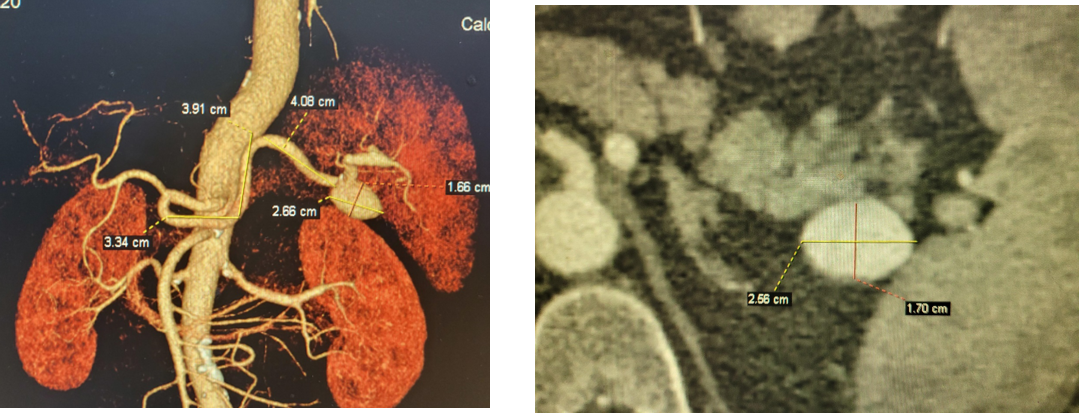

病例1 动脉瘤栓塞

2

病例2 分支栓塞+瘤腔栓塞